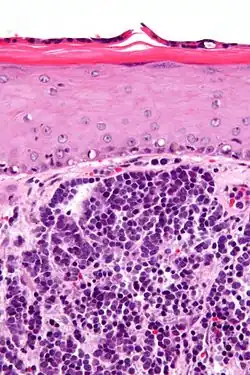

Micrograph of a Merkel cell carcinoma. H&E stain.

Diagnosis of MCC begins with a clinical examination of the skin and lymph nodes to determine suspicious areas for further investigation.[28] Definitive diagnosis requires examination of biopsy tissue to identify its histopathologic features.[6][28] An ideal biopsy specimen is either a punch biopsy or a full-thickness incisional biopsy of the skin including full-thickness dermis and subcutaneous fat. On light microscopy, MCC shows basaloid tumor nests with neuroendocrine features ("salt and pepper" chromatin, scarce cytoplasm, and brisk mitotic activity).[6][28] In addition to standard examination under light microscopy, immunohistochemistry (IHC) is also generally required to differentiate MCC from other morphologically similar tumors such as skin metastases of small cell lung cancer, the small cell variant of melanoma, various cutaneous leukemic/lymphoid neoplasms, and Ewing's sarcoma. Neuroendocrine molecular markers such as synaptophysin or chromogranin A are characteristic of MCC and other neuroendocrine tumors, while other markers such as PAX5 or cytokeratin 20 can distinguish MCC from these tumors.[3][7] Longitudinal imaging may also help in ruling out a diagnosis of metastatic small cell lung cancer. Once an MCC diagnosis is made, a sentinel lymph node biopsy as well as imaging are recommended as a part of the staging process, which determines prognosis and subsequent treatment options.[6][28] Imaging may include positron emission tomography or CT scan.[29]